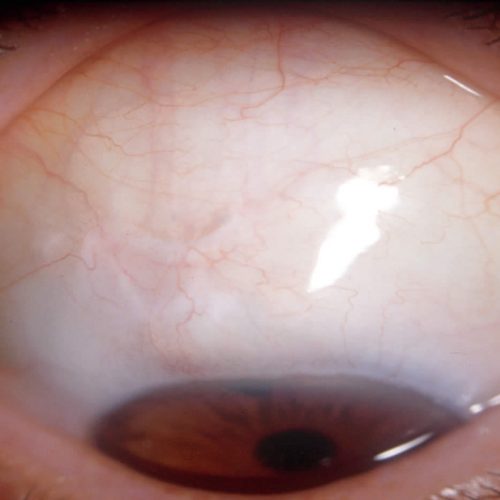

Phacoemulsification Cataract

Phacoemulsification is a modern-day cataract surgery that employs ultrasound energy to emulsify the nucleus, vacuum to catch the nuclear material, and irrigation and aspiration for cortex and viscoelastic removal. A typical phaco machine consists of a handpiece, foot pedal, irrigation